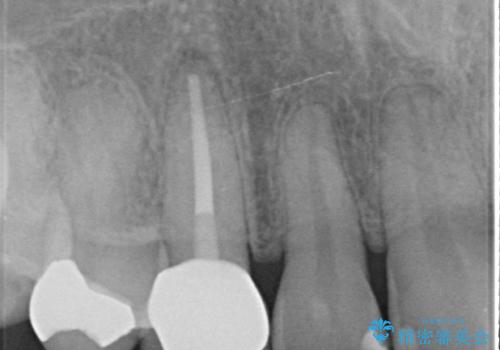

- 他院にて根管治療を行ったが疼きが治まらないため、当院にいらっしゃった方の症例です。

再根管治療を行い症状が治まったのを確認後、オールセラミッククラウン(スペシャル)による補綴を行いました。

- オールセラミッククラウン(スペシャル)…¥130,000、仮歯…¥10,000、ファイバーコア…¥20,000、精密根管治療費別途費用は治療当時の料金となります